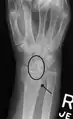

X-ray images indicate scapholunate ligament instability when the scapholunate distance is more than 3 mm, which is called scapholunate dissociation.[7] A static scapholunate instability is generally readily visible, but a dynamic scapholunate instability can only be seen radiographically in certain wrist positions or under certain loading conditions, such as when clenching the wrist, or loading the wrist in ulnar deviation.[6]

In order to diagnose a SLAC wrist you need a posterior anterior (PA) view X-ray, a lateral view X-ray and a fist view X-ray.[8] The fist X-ray is often made if there is no convincing Terry Thomas sign. A fist X-ray of a scapholunate ligament rupture will show a descending capitate bone. Making a fist will give pressure at the capitate, which will descend if there is a rupture in the scapholunate ligament.

Dynamic instability: Increased scapholunate distance (between yellow lines) upon ulnar deviation of the wrist, but not otherwise.

Dynamic scapholunate instability visible upon clenching the wrist

Scapholunate ligament disruption associated with a Colles' fracture